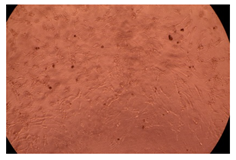

The results of the cytotoxicity assay, given in Figure 5, indicate that the tested PMs at all three established concentrations (10, 50, and 100 µg/mL) did not show cytotoxic effects on fibroblast cells at either 24 or 48 h after incubation. The percentages of cell viability were high, over 90%, in cells that were exposed to a concentration of 10 µg/mL for 24 h for all tested materials. Even at 48 h after incubation, the percentage of cell viability was as high as 90.4% in cells exposed to a concentration of 10 µg/mL for the Cop B sample. For both drug-loaded PMs, the cell viability decreased slightly at all tested concentrations. It also appears that the Dorzolamide-loaded PMs have slightly lower cell viability as compared to IMC-loaded PMs. Micrographs of the fibroblast cells after incubation times of 24 and 48 h are provided in Table 2.

Table 2.

Micrographs of fibroblast cells after 24 and 48 h incubation times, respectively.

As the cell viability values are all over 80%, the results indicate that the PMs, at the established concentrations, can be used successfully for in vivo biomedical applications.